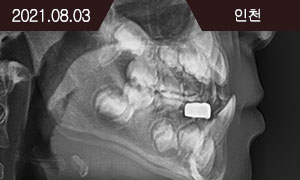

Face-mask를 이용한 골격성 III급 부정교합의 악정형치료

치료 과정

BEFORE

2020.12.12